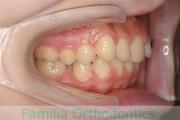

No.17V-308

- 過蓋咬合

- 叢生

- 8歳

- 女性

- FEA

- 90万円

出っ歯とかみ合わせを治したいとのことで小学生の時に来院されました。一期治療ではリップバンパーのみで経過を観察し、中学生の時に再診断をしました。やや叢生(でこぼこ、ガタガタ)がきつめでしたが、拡大・非抜歯・マルチブラケット法にて治療を行いました。二期治療は、2年半、30回の通院が必要でした。

非抜歯治療を行いましたので、後戻りのリスクが高めですので、保定観察が重要です。